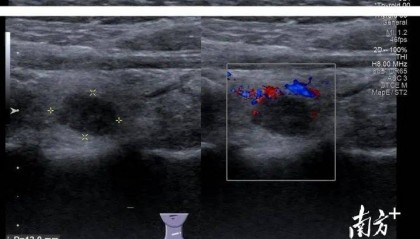

从东北到梅州,跨越3000公里的求医之路……

小罗是一名在校女大学生,家住在吉林省白城市,近期体检中发现甲状腺有个结节,彩超提示为C-TIRADS...